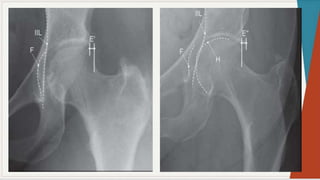

Radiografia Simples:

◗ Incidência ântero-posterior:

observar

as

características: espaços

articulares e

linhas

seguint

es

pélvica

s,

presença de qualquer doença óssea, ângulo colo-

diafisário, forma da cabeça femoral, presença de

osteófitos, evidência de fratura ou luxação,

evidência de deformação pélvica.

Radiografia Simples: ◗ Incidênciaântero-posterior: observar as características: espaços articulares e linhas seguint es pélvica s, presença de qualquer doença óssea, ângulo colo- diafisário, forma da cabeça femoral, presença de osteófitos, evidência de fratura ou luxação, evidência de deformação pélvica.